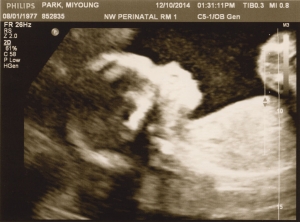

Last Ultrasound